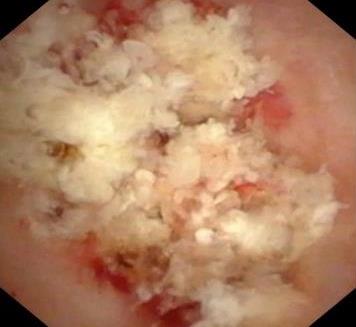

• 色素内镜和窄带成像技术联合放大内镜对早期结直肠癌及癌前病变的诊断价值研究

2026, 32(1):35-41. DOI: 10.12235/E20250020

摘要:目的 探究色素内镜(CE)和窄带成像技术(NBI)联合放大内镜(ME)对早期结直肠癌及癌前病变的诊断价值研究。方法 选取2023年8月-2024年7月于该院接受检查的疑似早期结直肠癌及癌前病变的患者160例。采用四格表法,分析NBI-ME和CE-ME检测早期结直肠癌及癌前病变的敏感度、特异度和准确度;采用Kappa一致性检验,分析CE-ME和NBI-ME诊断早期结直肠癌及癌前病变与病理检查的一致性。结果 病理结果显示,良性病变52例,癌前病变90例,结直肠癌18例。CE-ME检测结果显示,良性病变43例,癌前病变101例,结直肠癌16例,漏诊率为33.33%;CE-ME诊断早期结直肠癌及癌前病变与病理检查的一致性中度(Kappa = 0.605,P < 0.01),敏感度为66.67%,特异度为97.18%,准确度为93.75%。NBI-ME检查结果显示,良性病变43例,癌前病变100例,结直肠癌17例,漏诊率为16.67%,NBI-ME诊断早期结直肠癌及癌前病变与病理检查的一致性较高(Kappa = 0.714,P < 0.01),敏感度为88.33%,特异度为98.59%,准确度为96.88%。CE-ME与NBI-ME两者联合检查结果显示,良性病变56例,癌前病变86例,结直肠癌18例,漏诊率为5.56%,两者联合诊断早期结直肠癌及癌前病变与病理检查的一致性极高(Kappa = 0.857,P < 0.01),敏感度为94.44%,特异度为99.30%,准确度为98.75%,高于CE-ME和NBI-ME单独检查。结论 CE和NBI联合ME对早期结直肠癌及癌前病变具有较高的诊断价值。值得应用于临床。